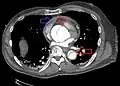

| Stanford type B dissection of the descending part of the aorta (3), which starts from the left subclavian artery and extends to the abdominal aorta (4). The ascending aorta (1) and aortic arch (2) shown in the image are not involved in this condition. | |

CT with contrast demonstrating aneurysmal dilation and a dissection of the ascending aorta (type A Stanford)- Chest CT with descending (type B Stanford) aortic dissection (red circle)